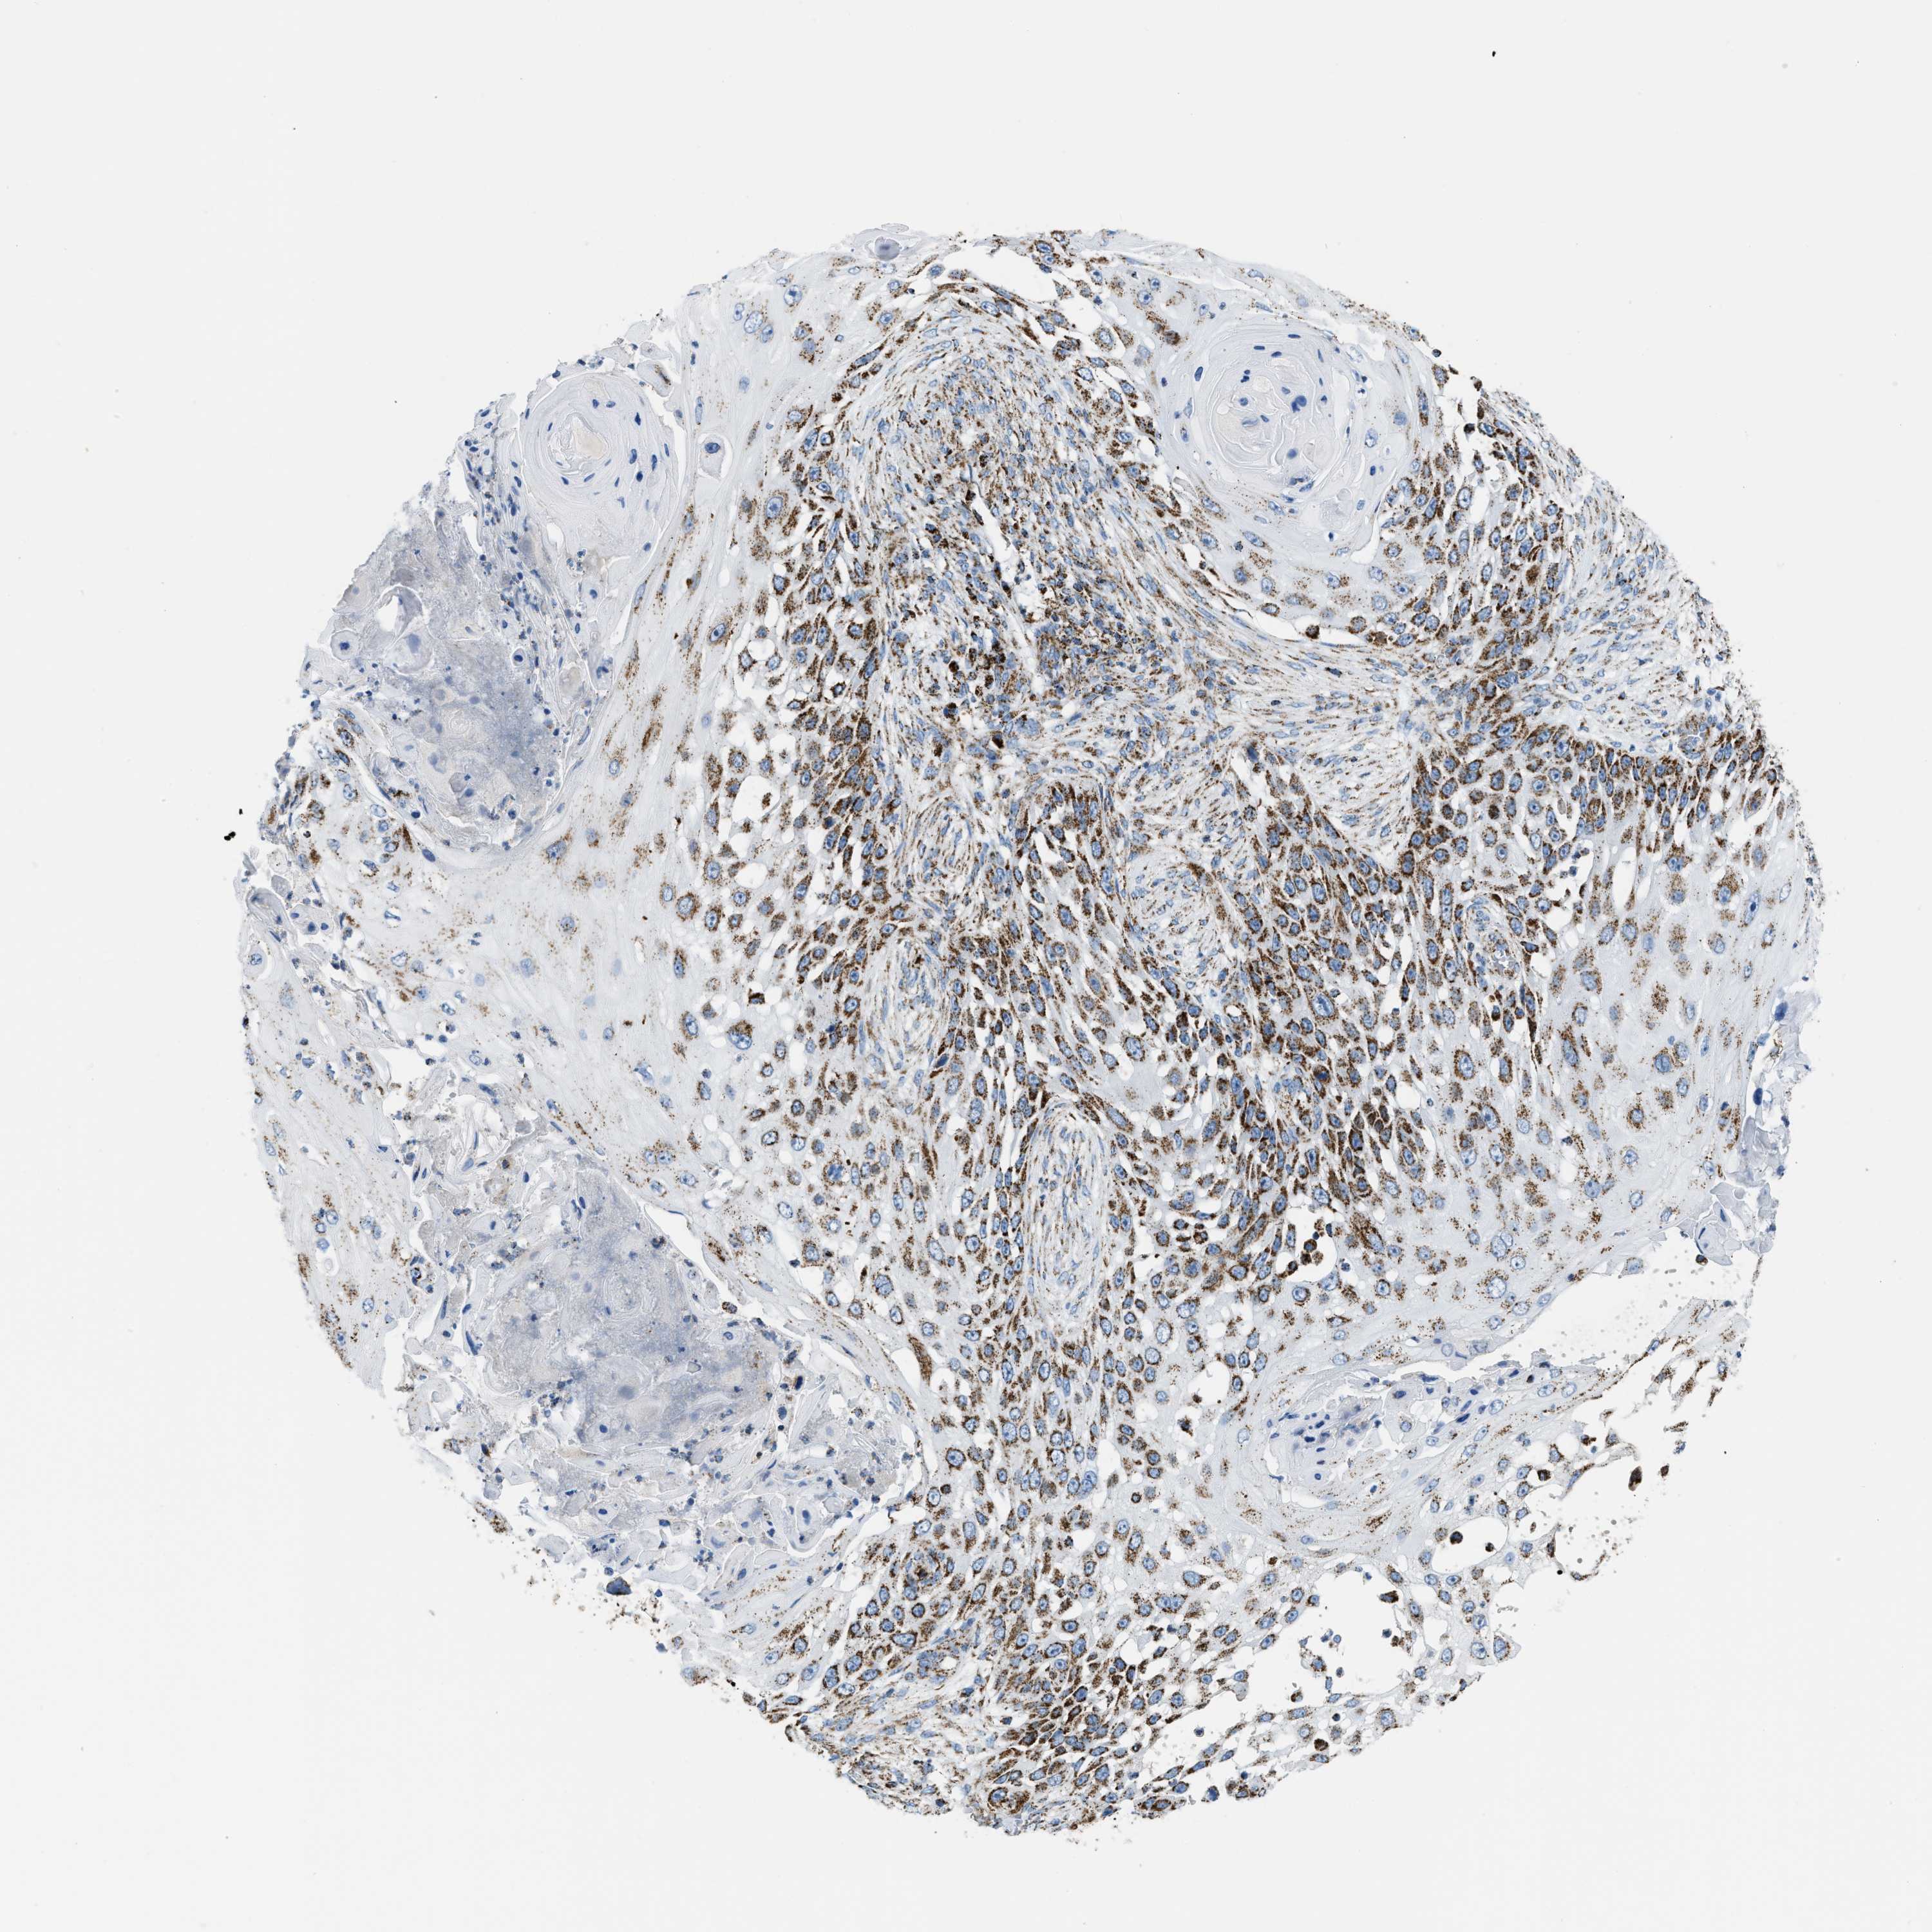

SKIN CANCER - Protein expressioni

A mouse-over function shows sample information and annotation data. Click on an image to view it in a full screen mode. Samples can be filtered based on level of antibody staining by selecting one or several of the following categories: high, medium, low and not detected. The assay and annotation is described here.

Each image is clickable and will lead to virtual microscopy that enables deeper exploration of all samples and also displays staining intensity scores, fraction scores and subcellular localization as well as patient and tissue information for each sample.

Antibody HPA018923

Squamous cell carcinoma, metastatic, NOS